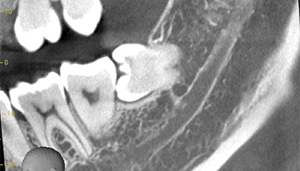

右下の親知らずが疼く症例

- 抜歯前写真(レントゲン)

- 抜去歯の写真(CT画像)

| 年齢 | 30代・女性 |

|---|---|

| 主訴 | 右下親知らずが疼く |

| 親知らずの生え方 | 横向きに生えている |

| 抜歯時間 | 40分 |

| 費用 | 約8,000円(保険診療、CT代含む) |

| 抜歯内容 | 右下の親知らずは横向きに生えて埋まっているため、麻酔をし親知らずの奥に切開を入れて歯ぐきを開き、歯を囲んでいる骨を削り歯の頭部分を割って出してから、残った根の部分を取り出して抜歯は終了しました。 歯ぐきを切った部分は糸で縫っています。このケースでは根の先端が神経に近く麻痺のリスクがありましたが事前にCTを撮影し、神経との位置関係を確認していたため、麻痺が残ることはありませんでした。 約1週間後に糸取りを行い、その際も多少の痛みや腫れはありましたが後日その痛みも無くなりました。 |